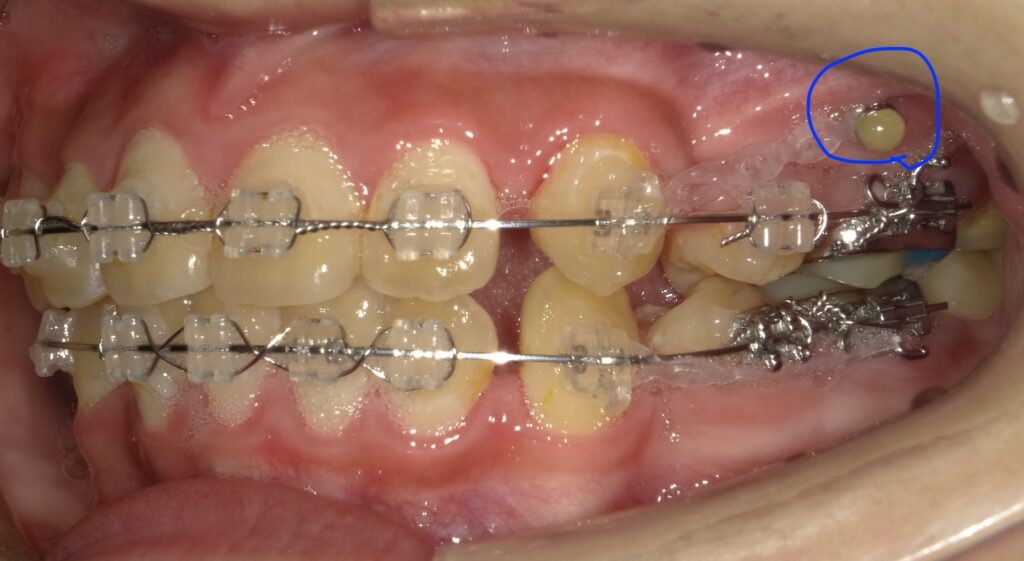

画像の青部分はアンカースクリューというネジでこれと

後ろに送りたい歯にゴムをつけて牽引します。